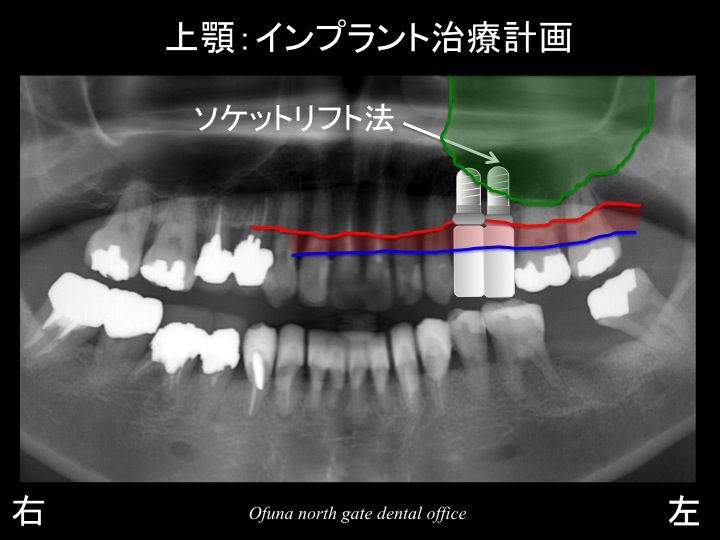

このままの状態で上顎左側の欠損部にインプラントを埋入すると

短いインプラントしか埋入できません。

短いインプラントは、安定が悪く長期的には問題が起こりやすいのです。

そこで少しでも長いインプラントを埋入する計画を立てました。

本日の最初にご説明したソケットリフト法 を応用したインプラントの埋入です。

詳細は、後で解説しますが、先にインプラント埋入後のレントゲンになります。

インプラント埋入後のレントゲン拡大を見てみましょう!

奥のインプラントの尖端に見える白っぽくなっているのがソケットリフト法 によって入れられた人工骨です。

このままでは、わかりづらいので、

骨の状態を赤線、

もともとの上顎洞の状態を緑線、

現在の上顎洞の位置を黄色線で表示します。

人工骨によって上顎洞が上方に押し上げられたのが分かるかと思います。